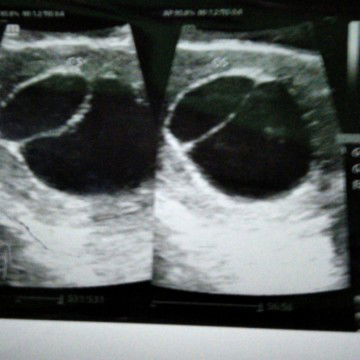

usg

Mau tny ada yg sma gk ya usg smalem hasil msh kantong usia kandungan 8week4d